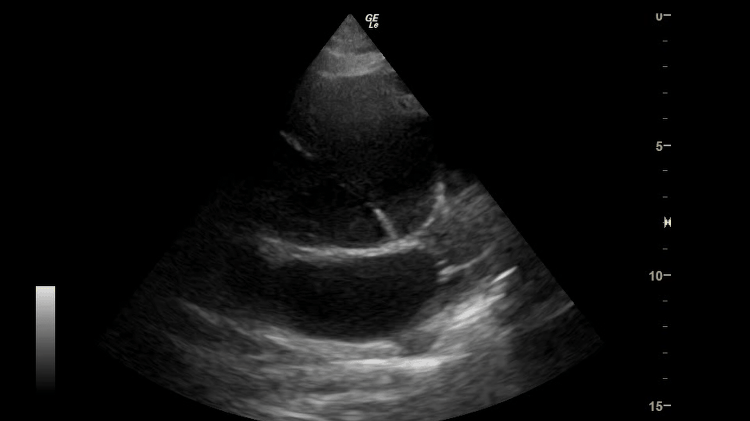

随后急诊医师对患者进行了CTA检查,结果CTA证实患者是主动脉A型夹层,后经及时抢救患者目前已成功手术。

▲CTA:主动脉A型夹层